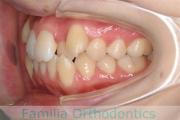

No.22V-498

- 上顎前突

- 側方偏位

- 年齢:

- 26歳

- 性別:

- 女性

- 抜歯部位

- 上:

- 44

- 下:

- 8|58

上の前歯が出ているのと下の前歯のでこぼこを治したいということで来院されました。左右のズレがあるので、上顎を左右から、下顎は左下のみ小臼歯を抜歯して、アンカースクリューを併用したマルチブラケット法にて治療を行いました。2年強、25回程度の通院が必要でした。

前歯の移動量が多いケースとなりますので、歯根吸収や歯肉退縮のリスクが高めです。